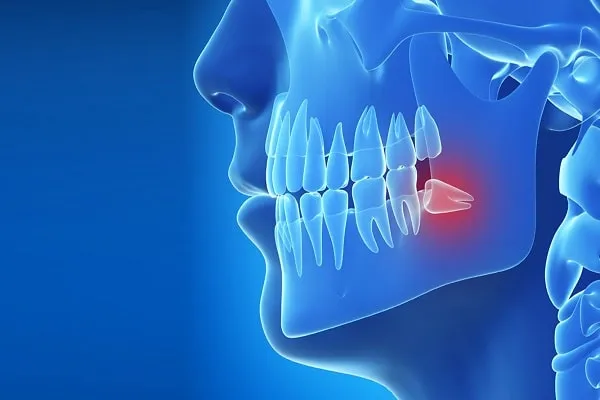

Gömülü Diş Operasyonları: Nedenleri, Süreci ve İyileşme Dönemi